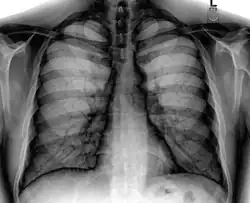

![]() A normal posteroanterior (PA) chest radiograph of someone without any signs of injury. Dx and Sin stand for "right" and "left" respectively. | |

A chest radiograph, chest X-ray (CXR), or chest film is a projection radiograph of the chest used to diagnose conditions affecting the chest, its contents, and nearby structures. Chest radiographs are the most common film taken in medicine.